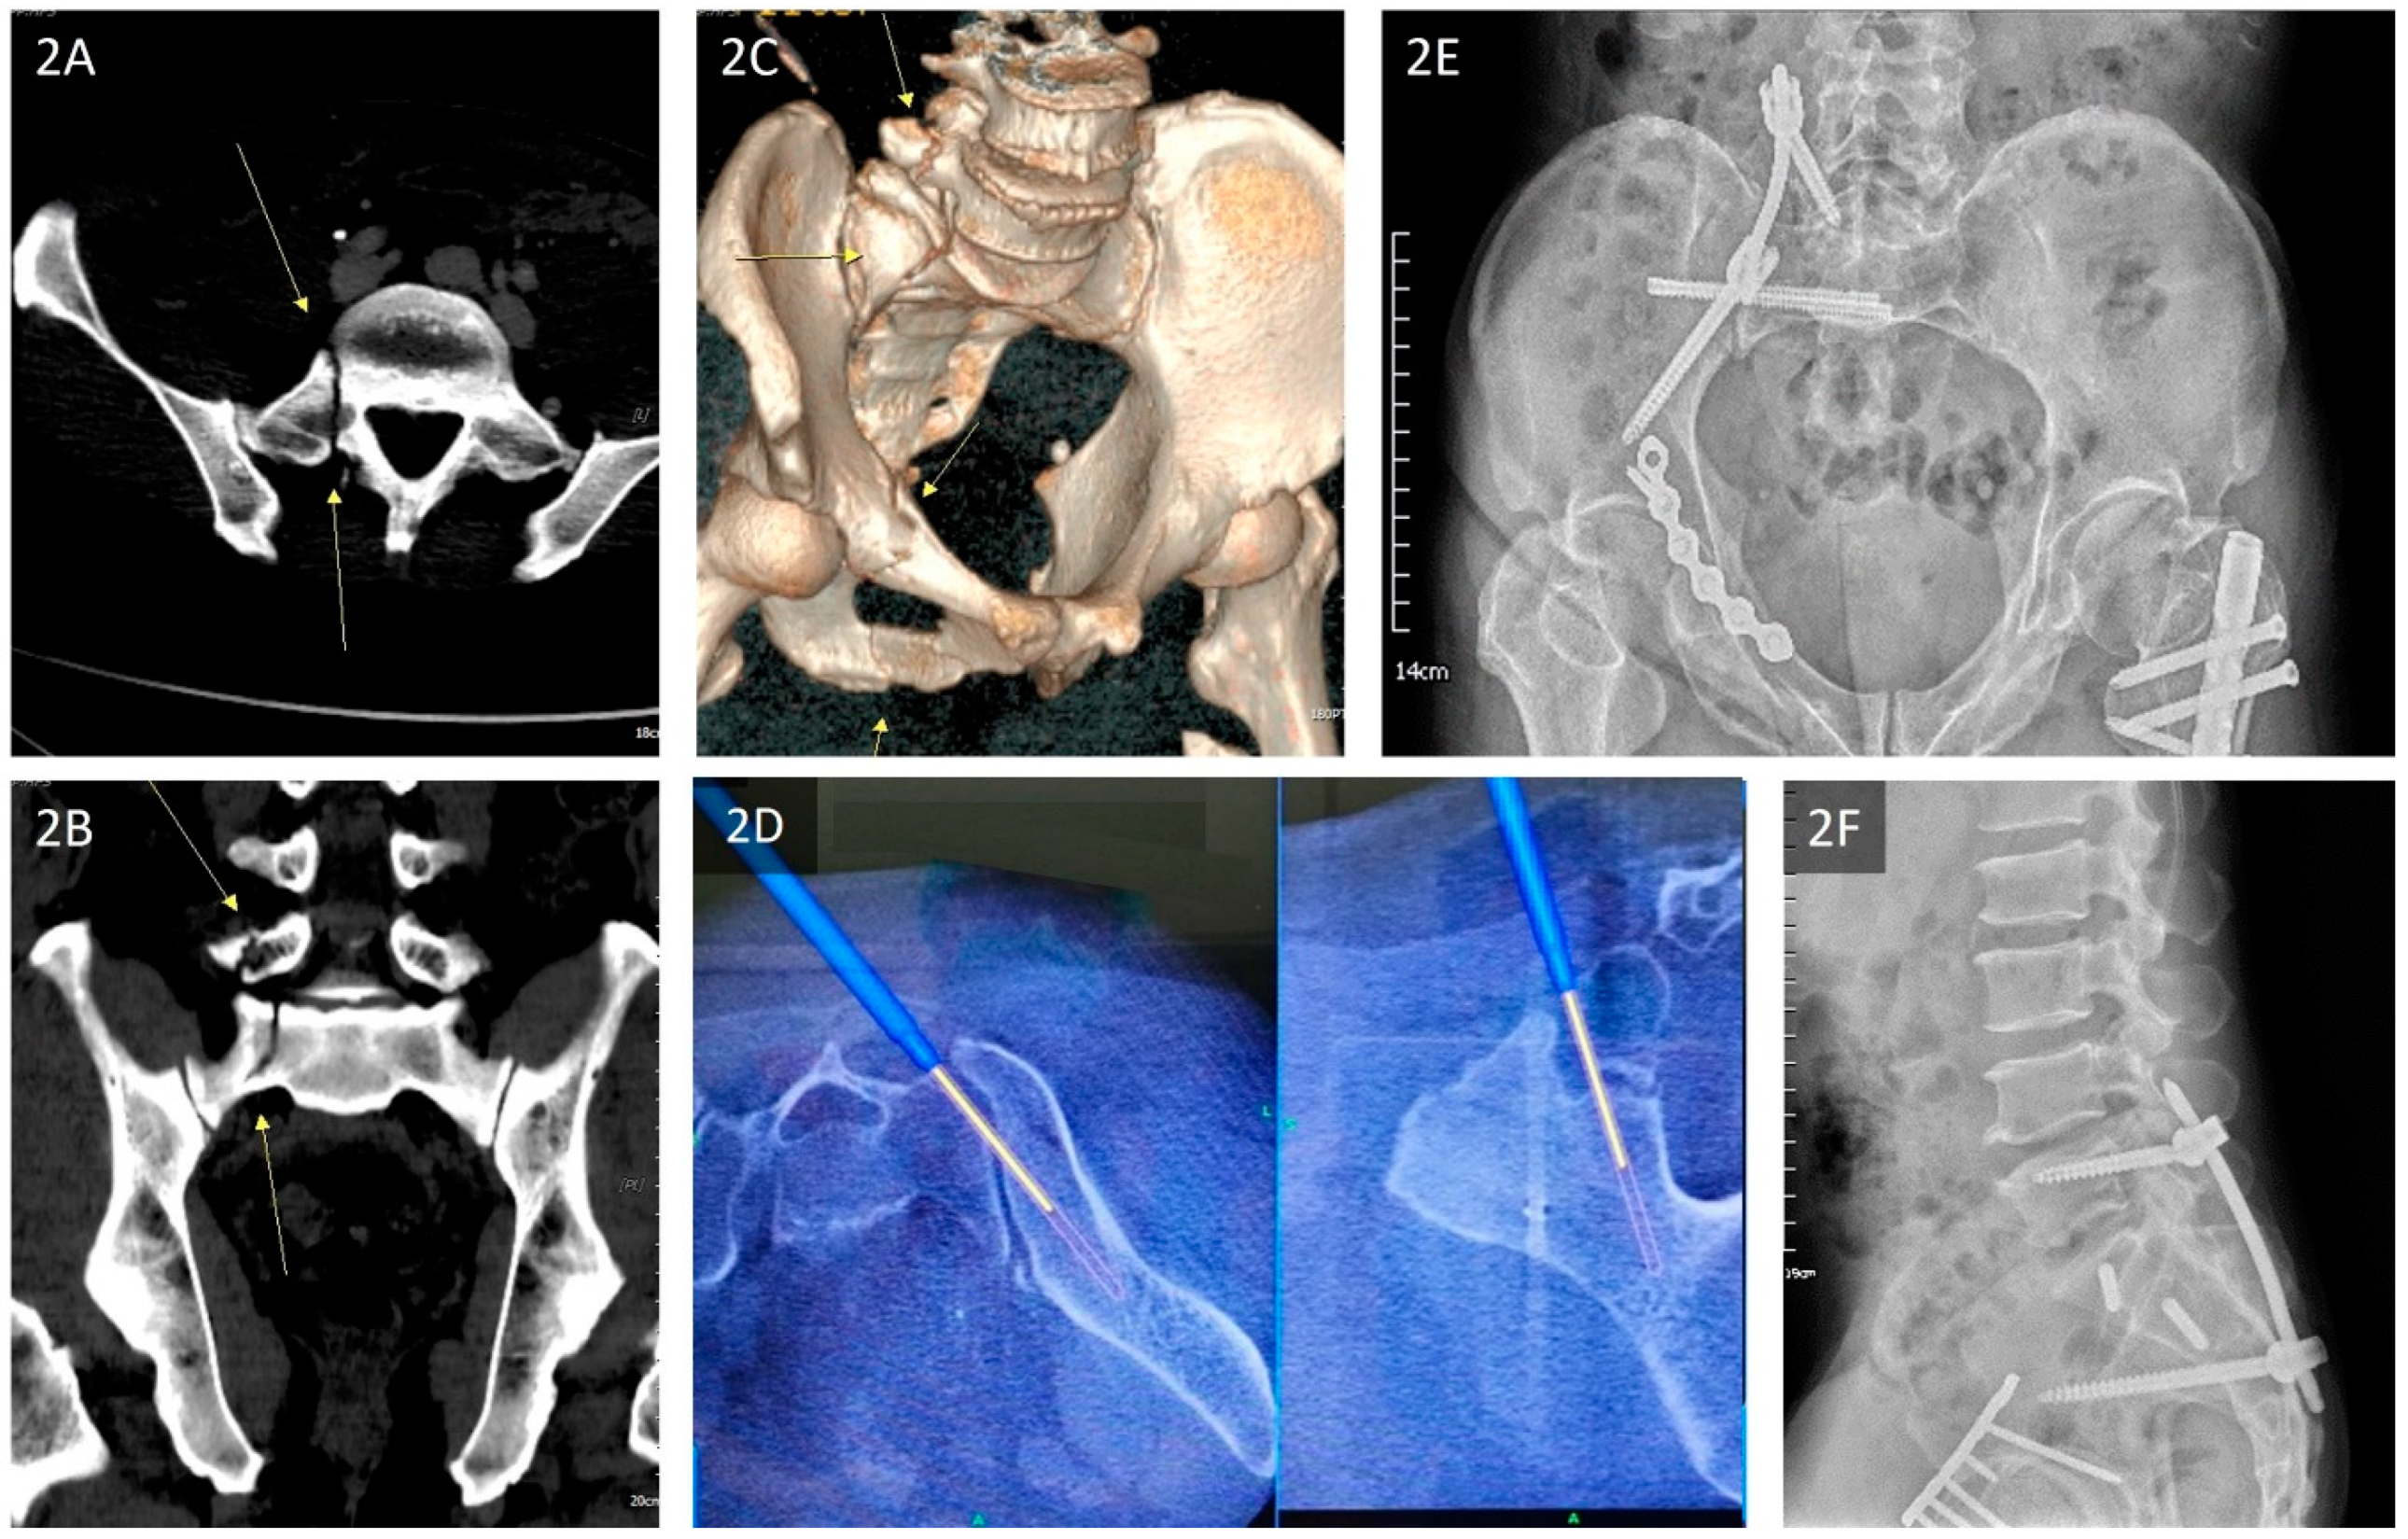

| Lefaivre et al., 2009 | Absolute displacement method (ADM) [13] | This method was initially proposed by Lefaivre et al. in 2009. Observers were instructed to use preoperative pelvic AP, inlet, and outlet views. In each view, a horizontal line was drawn across the superior end plate of L5 as a reference line. If this was not visible in the film, the observers were asked to use the inferior end plate of L5 as a reference. Measurements were either parallel or perpendicular to this reference line. This line was used as the direction for horizontal measurements, or a line 90 degrees to this reference line was used for vertical measurements. Maximum displacements in the anterior and posterior pelvic rings were measured in each plane film. After completing the six measurements of the three preoperative films (anterior and posterior rings in each of the AP, outlet, and inlet views), the observers were instructed to measure the same anatomic locations in the postoperative plane films. Finally, the largest single measurements from the six preoperative and postoperative measurements were considered the preoperative and postoperative maximum displacements, respectively (Figure 5A,B). |